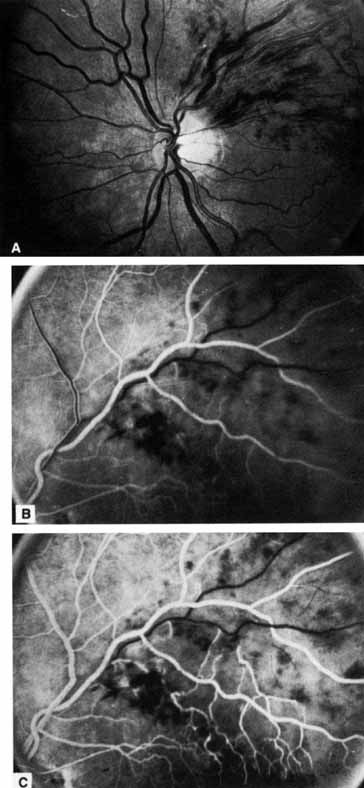

Fig. 2 A. Nonischemic central retinal vein occlusion. Note venous engorgement, dot, blot, and flame-shaped hemorrhages, blurring of disc margins, and a hemorrhage overlying the macula. B. Fluorescein angiogram reveals mild venous engorgement and tortuosity with virtually no capillary nonperfusion.

The ophthalmoscopic features of nonischemic central retinal vein occlusion are similar to those of ischemic central retinal vein occlusion, but are much less extensive (see Fig. 2; Fig. 3A and 3B). Engorgement of the venous tree (including the capillaries) is prominent; there is increased tortuosity and dilation and a darker appearance of the blood column. Retinal hemorrhages vary markedly. Sometimes they occur only peripherally; at other times, they may be rather prominent in the posterior pole.60 Cotton-wool spots are rare. Vision may be decreased because of macular edema or macular hemorrhage.

Fig. 3 A and B. Acute nonischemic central retinal vein occlusion in a 36-year-old hypertensive man. His visual acuity was 20/200. C and D. Six weeks later, he presented with eye pain, decreased vision, and neovascular glaucoma. The type of occlusion now is ischemic.

The angiographic pattern may show little except occasionally a prolonged venous transit time. Dilation of the retinal venous circulation, mild staining of the walls of veins, and varying degrees of disc and macular edema may be present (including cystoid macular edema). Capillary nonperfusion is not a prominent feature, nor is its sequela, neovascularization. The electroretinogram is nearly normal, confirming the lack of ischemia.77 The intraocular pressure is frequently lower on the side of the occlusion.78 Synonyms for this type of central retinal vein occlusion have included partial, incomplete, imminent, threatened, incipient, or impending central retinal vein occlusion.60,76 How many central retinal vein occlusions in this category are actually incomplete or partial occlusions that then progress to a more complete occlusion is unknown. It does appear that some eyes with nonischemic central retinal vein occlusion go on to develop a more ischemic type of central retinal vein occlusion (see Fig. 3); whether this represents a progression of the vein occlusion62 or simply progressive retinal capillary nonperfusion is unknown. In series in which the incidence of conversion for the nonischemic occlusion to the ischemic type has been studied, the incidence ranges from approximately 5% to 22%, depending on the duration of follow-up, and is higher for older patients.63,74,79–81

Patients with an ischemic pattern are usually aware of a sudden, painless decrease in visual acuity. Vision ranges from 20/400 to hand movements. The onset, however, is generally not as rapid or the visual loss as extensive as in central retinal artery occlusion. Exceptional cases have been noted in which patients with an acute onset had reasonably good vision and yet demonstrated a picture of ischemic central retinal vein occlusion. Patients with ischemic occlusion have an average age of 68.5 years.66 Confluent hemorrhages are the most prominent ophthalmoscopic feature of an acute ischemic central retinal vein occlusion (see Fig. 3C and 3D). These hemorrhages occur in a wide variety of shapes and sizes; they are usually concentrated in the posterior pole, but may be seen throughout the retina. Hemorrhages in the superficial retina may be so prominent about the posterior pole that the underlying retina is obscured. Many hemorrhages are flame shaped, reflecting the orientation of the nerve fibers. Dot and punctate hemorrhages are interspersed and indicate involvement of the deeper retinal layers. Bleeding may be extensive, erupting through the internal limiting membrane to form a preretinal hemorrhage or extending into the vitreous. Small dot hemorrhages may be seen either isolated or clustered around small venules. The entire venous tree is tortuous, engorged, dilated, and dark. The retina is edematous, particularly in the posterior pole; some of this edema may obscure portions of the retinal vessels. Cotton-wool patches (soft exudates) are often present.